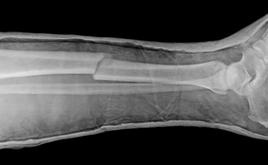

14. Огнестрельное ранение правого плеча с переломом плечевой кости расценивается как: |

| 1. Тяжкий вред, причиненный здоровью человека. 2. Средний вред, причиненный здоровью человека. 3. Легкий вред, причиненный здоровью человека. |

27. Закрытый перелом правой лучевой кости относится к повреждениям, причинившим вред здоровью средней тяжести по признаку_____ расстройства здоровья на срок свыше 3 недель.

1. Длительности.

28. Закрытый перелом диафиза большеберцовой кости квалифицируется как _________. |

| 1. Средний вред здоровью. 2. Тяжкий вред здоровью. 3. Легкий вред здоровью |

29. Перелом костей носа относится к повреждениям, причинившим _______ вред здоровью по признаку кратковременного расстройства здоровья на срок до 3 недель.

3. Легкий.